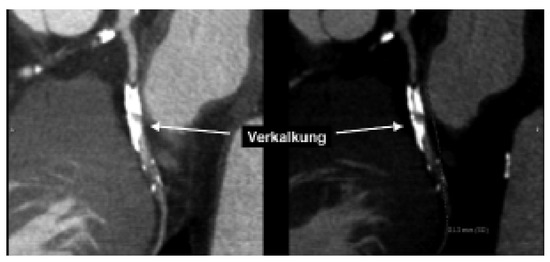

Biventricular pacing is an accepted therapy in patients suffering from terminal heart failure. Main obstacle however is the positioning of the left ventricular electrode via coronary sinus as well as its reliable fixation. This article describes in a...